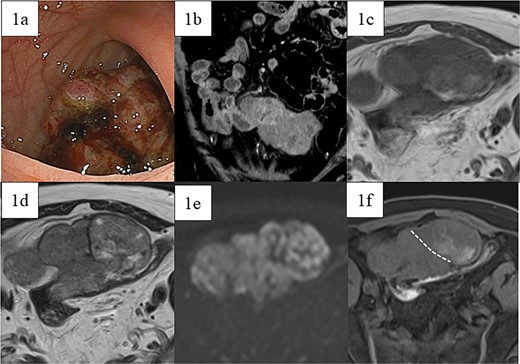

A 66-year-old male with a positive fecal occult blood test and lower abdominal pain underwent a lower gastrointestinal endoscopy, revealing a type 1 tumor in the sigmoid colon (Fig. 1a), though biopsies were inconclusive. Contrast-enhanced CT showed an 80 mm × 95 mm × 45 mm contrast-enhanced tumor adherent to the small intestine, with unclear origin (Fig. 1b). Magnetic resonance imaging (MRI) indicated a heterogeneous tumor with low-intensity areas on T1 and T2 and high intensity on diffusion-weighted images (Fig. 1c–e). Contrast-enhanced MRI revealed two areas with different contrast effects (Fig. 1f). Differential diagnoses included adenocarcinoma, GIST, sarcomas, and lymphomas, leading to resection.

Preoperative images. (a) Lower gastrointestinal endoscopy revealed a type 1 tumor in the sigmoid colon. (b) Contrast-enhanced computed tomography showed a contrast-enhanced soft-tissue tumor measuring 80 mm × 95 mm × 45 mm (arrow), which was partially adherent to the small intestine. MRI showed a tumor that was heterogeneous in both (c) T1- and (d) T2-weighted images with predominantly low-intensity areas, with some high-intensity areas in T2. (e) Diffusion-weighted images showed high intensity throughout the entire tumor. Contrast-enhanced MRI (f) showed two areas with slightly different contrast effects. White dotted lines indicate boundaries of the areas with different contrast effects.